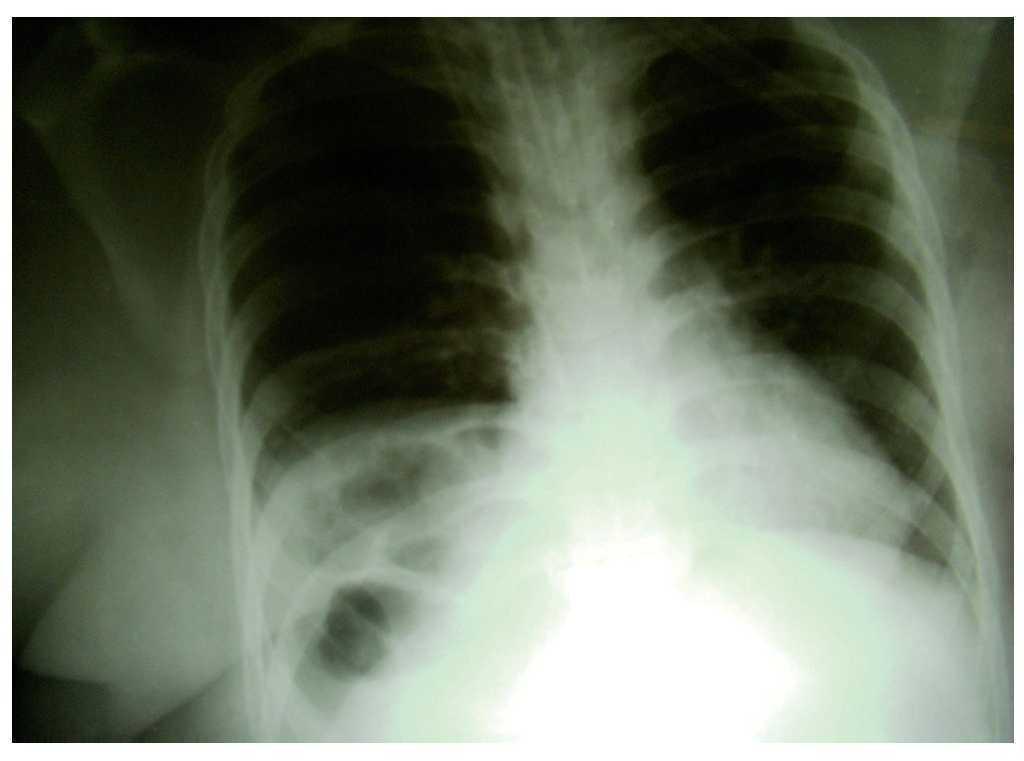

Un cop a la planta, va rebre tractament amb oxigen nasal. El tractament amb levofloxacina es va interrompre el catorzè dia de tractament. El segon dia de seguiment a la planta es va observar un desenvolupament progressiu de dispnea i cianosi. Es va tornar a traslladar la pacient ràpidament a l'UCI amb la sospita d'una recidiva de l'HD i la possibilitat d'un ràpid deteriorament clínic. La pacient es va sotmetre a oxigenoteràpia i a un seguiment exhaustiu. La radiografia toràcica va tornar a revelar segments intestinals al costat dret de la cavitat toràcica. Durant el seguiment no es va requerir cap més reemplaçament invasiu d'oxigen i l'acidosi respiratòria va remetre amb mascareta facial d'oxigen. El mateix dia de l'ingrés, en la radiografia toràcica es va observar que les nanses intestinals havien desaparegut. Després de la millora clínica de la pacient, es va traslladar a la planta de cirurgia per sotmetrela a una altra operació per l'hèrnia recurrent, de perill vital.

El diagnòstic d'hèrnia es realitza amb una radiografia del tòrax i visualitzant el contingut abdominal herniat a la cavitat toràcica, i la modalitat de tractament definitiva és la cirurgia. En el cas que ens ocupa, s'observaren segments d'intestí herniats a la radiografia toràcica inicial. A causa del deteriorament clínic progressiu, es van haver de fer més exploracions radiològiques, tot i que no es van detectar altres vísceres en la cavitat toràcica.